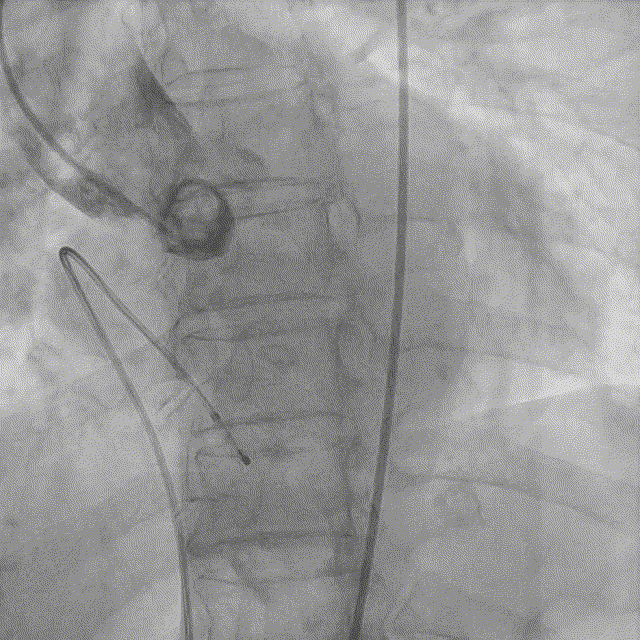

主动脉根部造影

5. AL2导管配合直头超滑导丝跨瓣;

6. 20mm球囊预扩张;

球囊预扩张